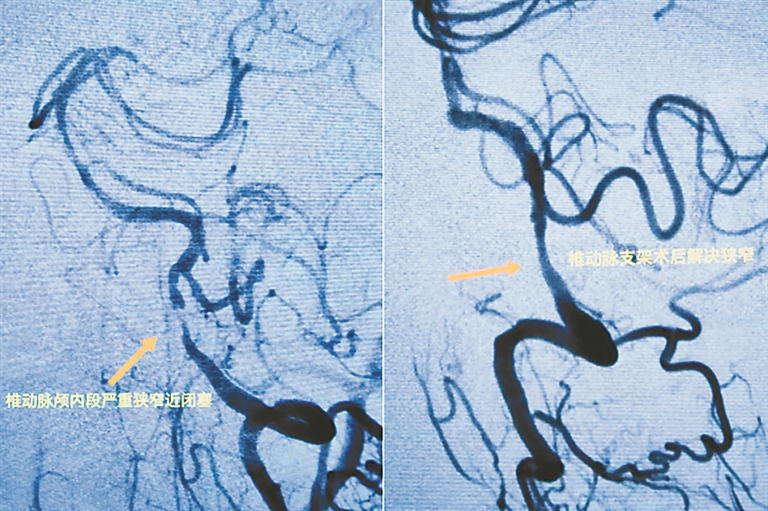

“正常情况下,脑梗不会发作这么频繁,这说明老人还是有病变的地方。我怀疑之所以反复发作,有可能是椎动脉颅内段重度狭窄病变。”神经外一科孙国章主任医师说。经进一步检查,果然,李大爷不仅椎动脉颅内段有重度堵塞,且左侧颈动脉也堵得很严重,两处都已经几乎全堵住了。

毛铁副主任医师与孙国章主任医师商议后,决定同时治疗两处病变。手术过程非常顺利,医生为李大爷植入两枚支架,两处致命的堵点当即被打开。目前,李大爷已痊愈出院,老毛病没有复发。